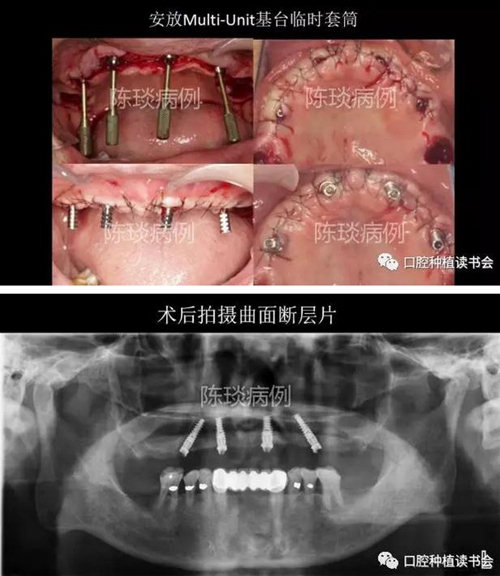

5,種植外科流程:

(1)數(shù)字化導板引導下完成種植體植入。

8.jpg

9.jpg

10.jpg

(2) 種植體植入術后制作臨時修復體即刻修復。